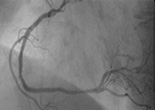

Dilatation und Stentimplantation

Ballonaufdehnung eines Herzkranzgefäßes und Einlage einer Gefäßstütze.